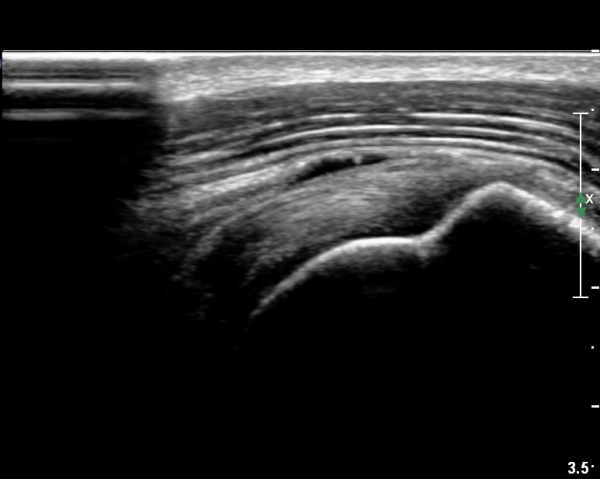

ÃÊÀ½ÆÄ ¼Ò°ß :  È¸Àü±Ù°³°£°Ý °Ë»ó»ó ±Ø»ê°ÇÀº Á¤»ó¼Ò°ßÀ» º¸À̳ª °ß°©ÇϱٰÇÀº Àú¿¡ÄÚ ¿¬°á¼º ¼Ò½ÇÀÌ

º¸¿© °ß°©ÇÏ±Ù°Ç ÆÄ¿­ÀÌ ÃßÁ¤µÈ´Ù(»çÁø 1). ŽÃËÀÚ¸¦ ¾à°£ ¾Æ·¡·Î À̵¿ÇÑ ÈÄ

ÆÈÀ» ¿ÜȸÀüÇϸ鼭 °üÂûÇÏ´Ï °ß°©ÇÏ±Ù°Ç ÆÄ¿­ÀÌ ¶Ñ·ÈÇÔ(»çÁø 2, 3).